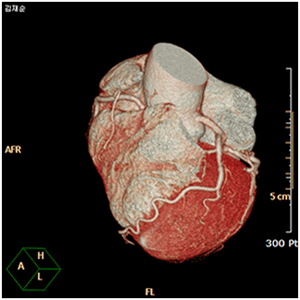

심장 및 혈관 영역에서는 관상동맥 질환, 판막 질환 및 대동맥 박리와 같은 심혈관 질환에대한 수술 이외에도 말초혈관의 폐색증, 하지의 정맥류 질환과 같은 말초혈관 질환의 외과적·내과적 치료를 시행하고 있습니다.

관상동맥 환자의 3D-CT